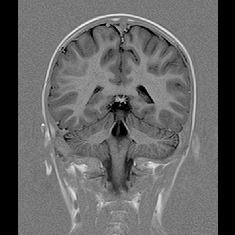

脳血管疾患や脳腫瘍などの脳疾患の有無を調べる検査として、一般的に、頭部CT、MRI、MRAと頸部MRA、頸動脈エコーなどが用いられています。

① MRI

② MRA